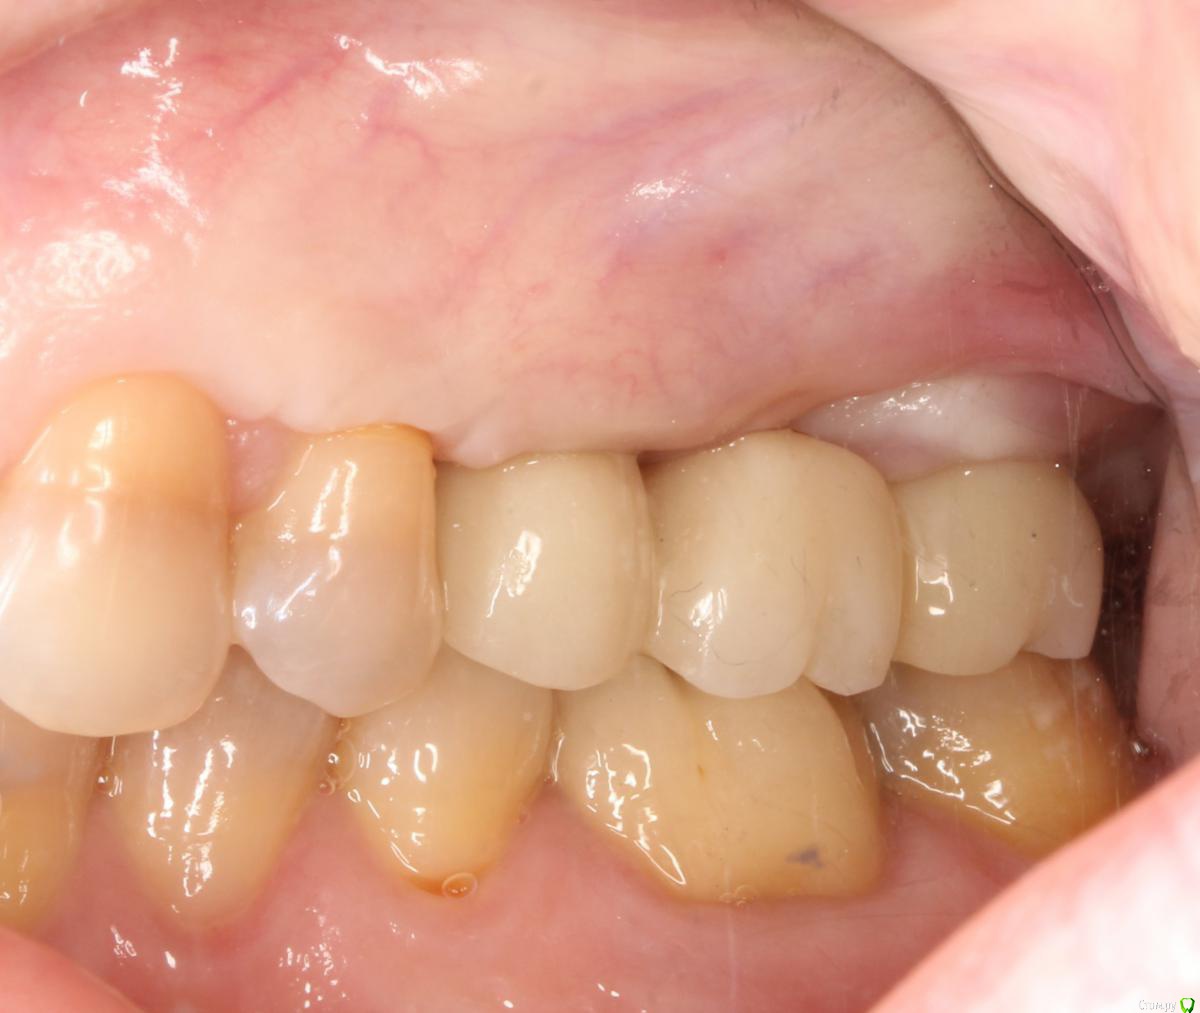

это времянки, постоянная - средний ряд, правая сторона, последнее фото

Ааа, теперь понятно. А то я думаю, почему какие-то фото отзеркалены, а другие нет... думал, что разные стороны)

Ну тогда вообще все здорово!